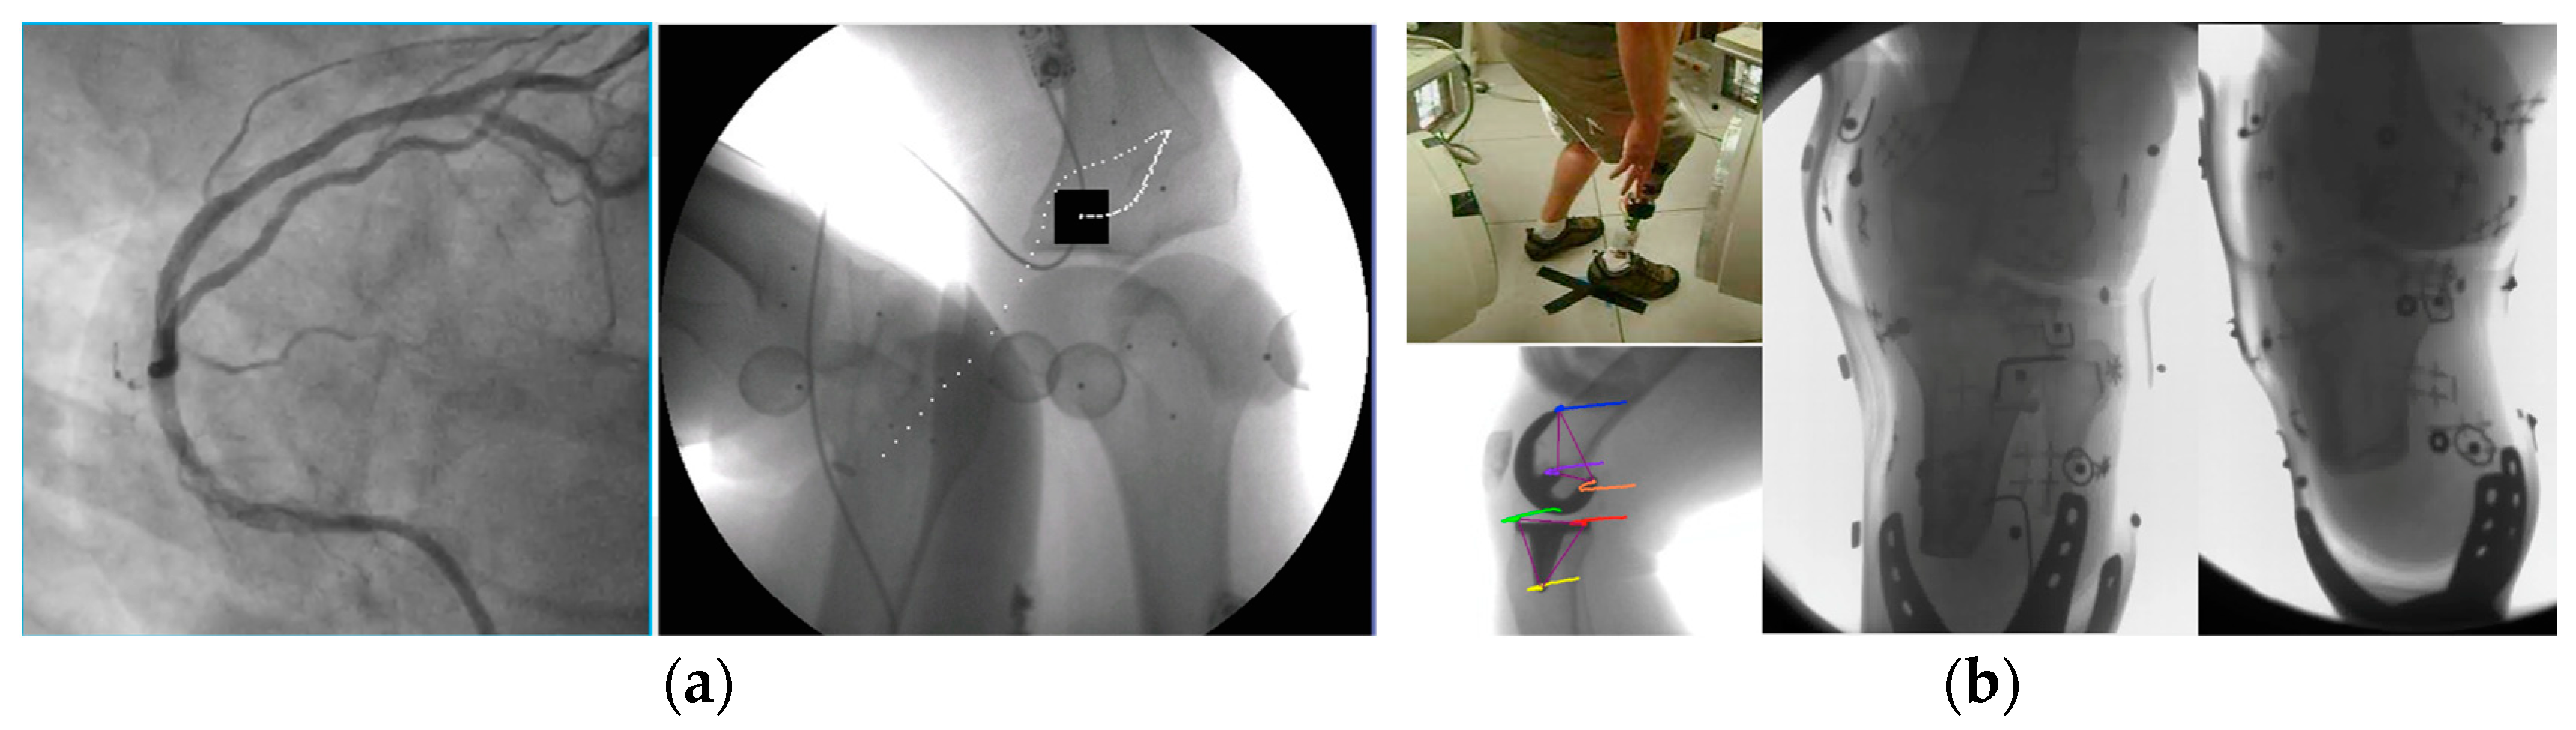

| 3D dynamic imaging stereovideography (Figure 5, Figure 6 and Figure 9) | 20–200 μm Static or moving image intensifiers with high-speed cameras | 1 s, as required by IR/10–10000 | 0.02–1.1 mSv min−1/0.08–0.9 mSv min−1/0.02–0.08 mSv min−1 | 50–1100 /10–500/variable VD and VH/0.02–0.2 |